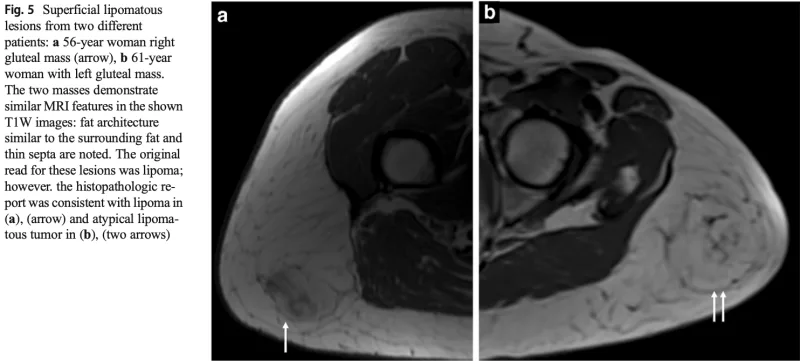

aは良性の脂肪腫, bは良悪性中間型の異型脂肪腫様腫瘍.

どちらも皮下脂肪との境界が不明瞭です.

MRIを撮像した結果, 皮下脂肪の肥厚を認めるものの, 腫瘍の再発かどうかは判断できませんでした.